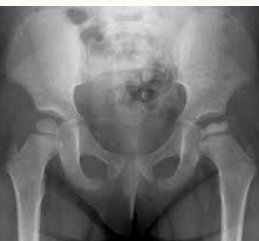

49

Dx?

slipped capital femoral epiphysis